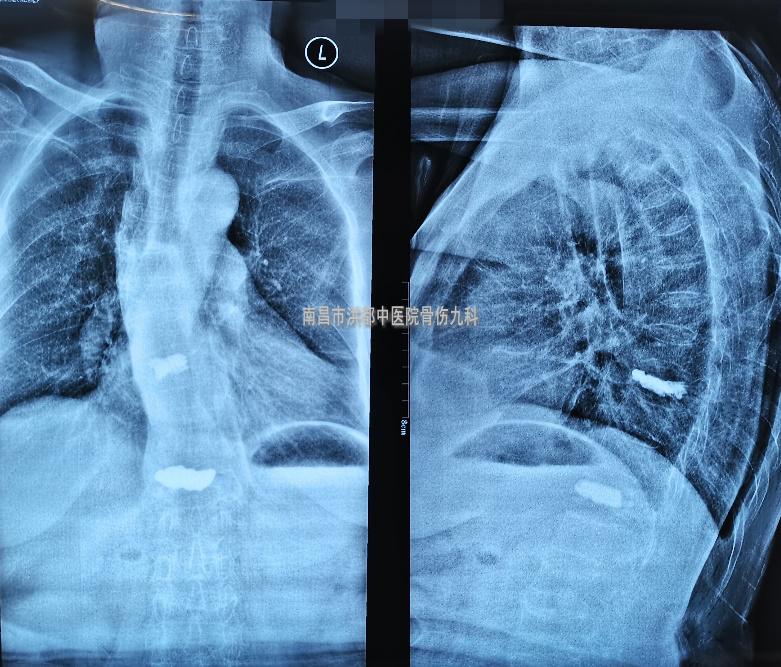

术前影像(磁共振提示:T9、T12椎体新鲜骨折)

骨伤九科副主任医师刘晓平详细询问病情及强烈建议下,还是拍了个X光片。不拍不知道,一拍吓一跳,原来钱婆婆的脊柱发生了压缩性骨折。

术后影像